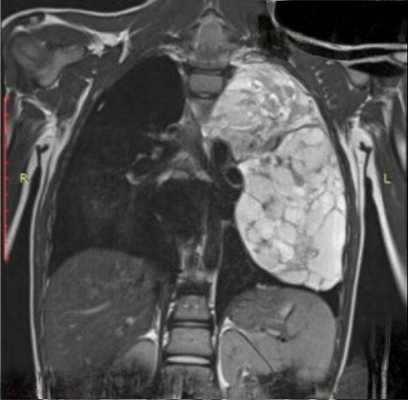

Средостение

В средостении в большинстве случаев присутствуют крупные опухоли, но при этом синдром сдавления верхней полой вены диагностируется редко.

Рисунок 6. — КТ органов грудной клетки - семинома средостения.

Гистологическая картина новообразования в основном смешанного происхождения, имеет тератоидный компонент и клетки, которые характерны для новообразования желточного мешка.